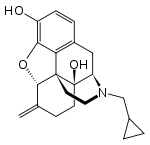

Several semi-synthetic opioids were developed in Germany in the 1910s. The first, oxymorphone, was synthesized from thebaine, an opioid alkaloid in opium poppies, in 1914.[228] Next, Martin Freund and Edmund Speyer developed oxycodone, also from thebaine, at the University of Frankfurt in 1916.[229] In 1920, hydrocodone was prepared by Carl Mannich and Helene Löwenheim, deriving it from codeine. In 1924, hydromorphone was synthesized by adding hydrogen to morphine. Etorphine was synthesized in 1960, from the oripavine in opium poppy straw. Buprenorphine was discovered in 1972.[228]